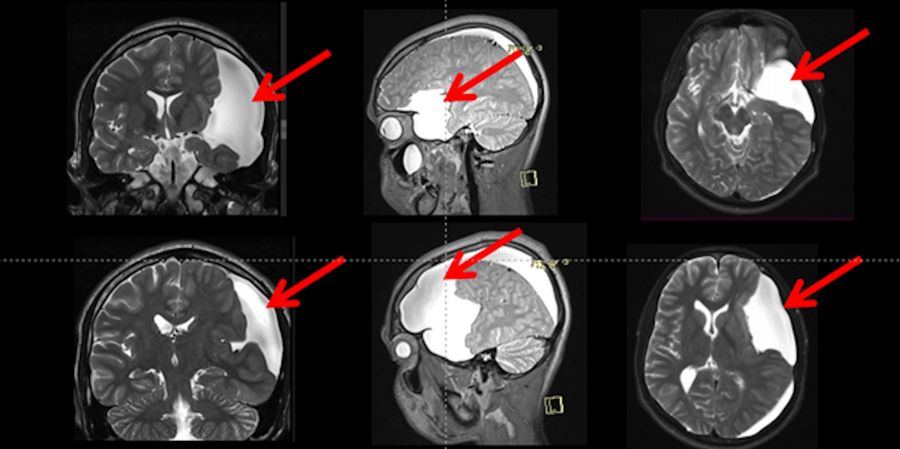

The T2WI revealed a large arachnoid cyst (represented by red arrows) on the left side with a hyper-signal when compared to the brain, including a similar signal compared to the cerebral spinal fluid.

Fig. 3: T2 weighted MRI showed a large arachnoid cyst (red arrows), Galassi III with a hyper-signal compared to the brain, and iso-signal when compared to the cerebrospinal fluid inside the ventricles. This cyst is compressing the adjacent brain and is not communicating with the Sylvian, carotid, and optic-Chiasmatic cisterns).

The patient had an uneventful follow-up with complete remission of symptoms. He was discharged from the ICU on the first postoperative day. On the second postoperative day, the patient underwent an MRI scan that revealed a normal flux from the cyst to the prepontine and interpeduncular cisterns, as demonstrated in Fig. 6 represented by red arrows. The patient was discharged on the third postoperative day.

Fig. 6: T2 weighted MRI image shows a normal flow from the cyst to the prepontine and interpeduncular cisterns.